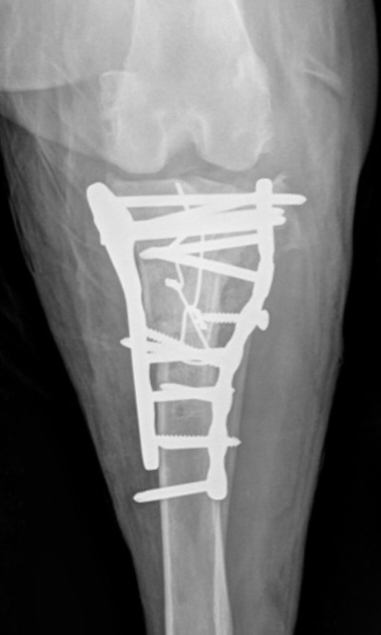

What would you do with this :-0 Our autumn meeting is all about...REVISION SURGERY! 20-22nd Nov in Bristol, full details and booking info shared here v soon :-)

What would you do with this :-0

Our autumn meeting is all about...REVISION SURGERY!

20-22nd Nov in Bristol, full details and booking info shared here v soon :-)